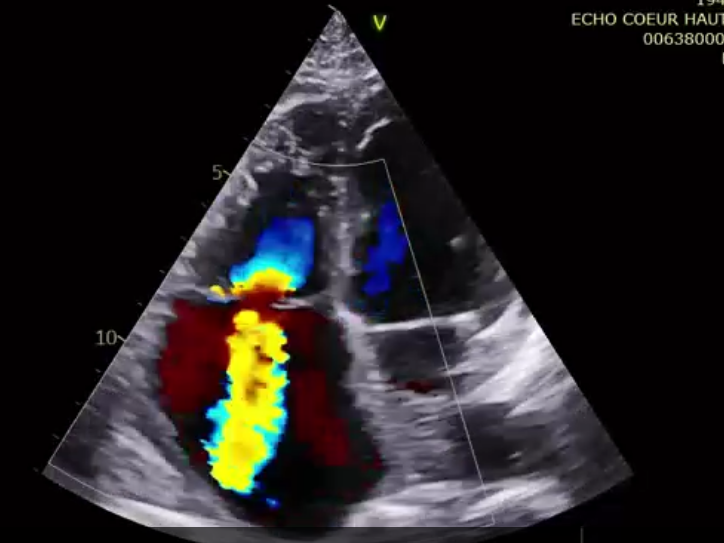

術(shù)前超聲提示大量三尖瓣反流